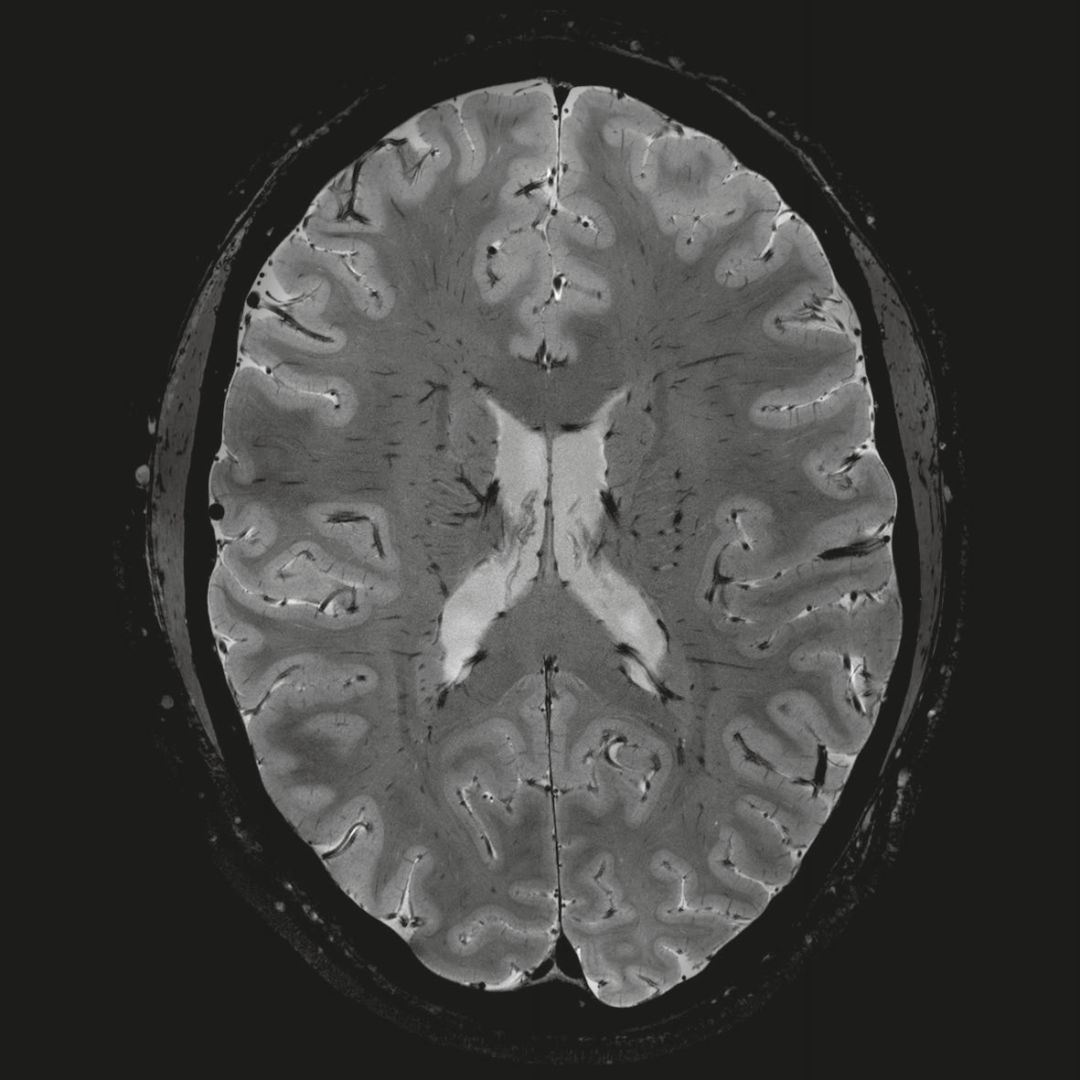

1毫米的各向同性分辨率DTI:神經(jīng)纖維束的交叉細(xì)節(jié)顯示

0.8毫米的各向同性分辨率:精確劃分灰質(zhì)和白質(zhì)

超精細(xì)的解剖細(xì)節(jié):T2對比

0.17 x 0.17 x 0.8毫米分辨率超高。